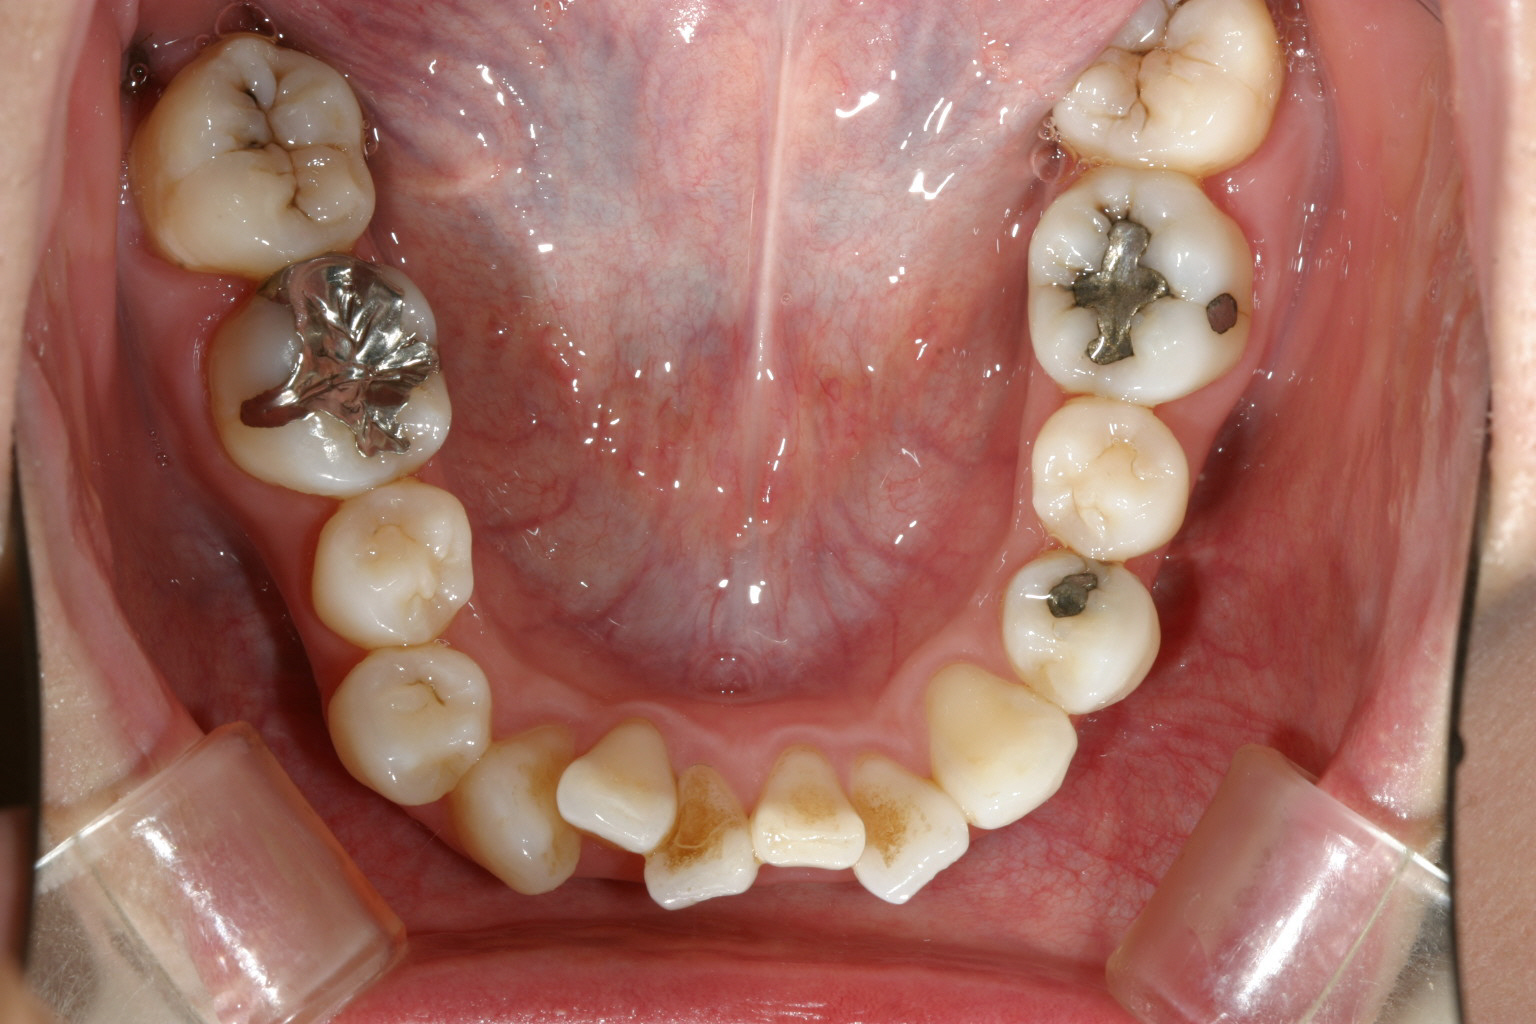

下顎前歯は犬歯間幅径が狭い為ヘビーなガタガタです。

治療1年半後にマルチループにて咬合の修正を行っています。 特に下顎の犬歯の歪みを早く改善したいです。

マルチループワイヤー入れて2ヵ月でここまで修正完了です。 下顎犬歯の歪みも改善しました。

下顎のガタガタも綺麗に改善しました。